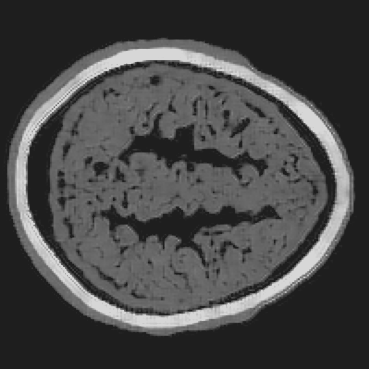

Refer to caption

(a) RCAN.

(b) LDM.

(c) ViT.

(d) BrainPuzzle.

(e) Ground Truth.

(f) RCAN.

(g) LDM.

(h) ViT.

(i) BrainPuzzle.

(j) Ground Truth.

Figure 10: Baseline comparison on partial-array data. Two axial slices: RCAN, LDM, ViT, and BrainPuzzle versus ground truth. BrainPuzzle preserves fine structure and boundary sharpness.

Table II summarizes the average performance over 50 slices of 2D brain images during the testing phase for both the full-transducer and partial-transducer datasets. The results demonstrate that the BrainPuzzle method outperforms all baseline models, achieving the highest SSIM values and the lowest RMSE values in both scenarios. Several key observations can be made: (1) We observe that the U-Net model and super-resolution baselines such as RCAN and CycleGAN achieve inferior performance compared to BrainPuzzle in terms of both SSIM and RMSE. These baseline models are less capable of handling the intricate spatial relationships and texture details required for accurate reconstruction, and thus struggle to effectively recover complete brain images. (2) BrainPuzzle also outperforms more advanced generative models, including LDM and ViT. While LDM and ViT exhibit more complex structures and training processes, they require significantly longer training and inference times compared to BrainPuzzle. Despite their complexity, these models fail to match the accuracy and efficiency achieved by BrainPuzzle, underscoring its robustness and practical applicability. (3) All models demonstrate significantly better performance on the full-transducer dataset compared to the partial-transducer dataset. This superiority is attributed to the clearer and more complete input brain fragments in the full-transducer scenario, which provide essential spatial information and finer-grained textures crucial for accurate reconstruction. In contrast, the partial-transducer data are not sufficient for high-quality reconstruction using limited and fragmented inputs.

The efficacy of the BrainPuzzle method is further demonstrated by the visual results presented in Fig. 10. These results showcase comprehensive brain images reconstructed across multiple 2D slices, highlighting the superior performance of the proposed method. A detailed analysis of these images reveals the following observations: (1) The RCAN baseline exhibits significant limitations in reconstructing the complete structural complexity of brain images. It struggles to capture the fine textures and intricate details characteristic of brain imagery, resulting in noticeably lower-quality reconstructions. (2) BrainPuzzle achieves a significant improvement in image quality, excelling in capturing finer details such as the accuracy of structural contours and the fidelity of textural patterns. These improvements can be particularly critical for medical diagnosis and analysis, where precision and detail play a pivotal role in ensuring reliable outcomes. (3) While LDM and ViT produce reasonably good results, they fall short of BrainPuzzle in accurately reconstructing smaller details. The minor deficiencies in their reconstructions highlight BrainPuzzle’s superior ability to preserve intricate features and deliver higher-quality outputs.